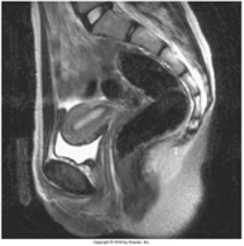

You are an X-Ray technician who works nights at a rural hospital. The doctor on call orders an MRI. You complete the order. Below is an image from the scan.

This anatomical plane divides the body into what structures?

What are right and left parts?